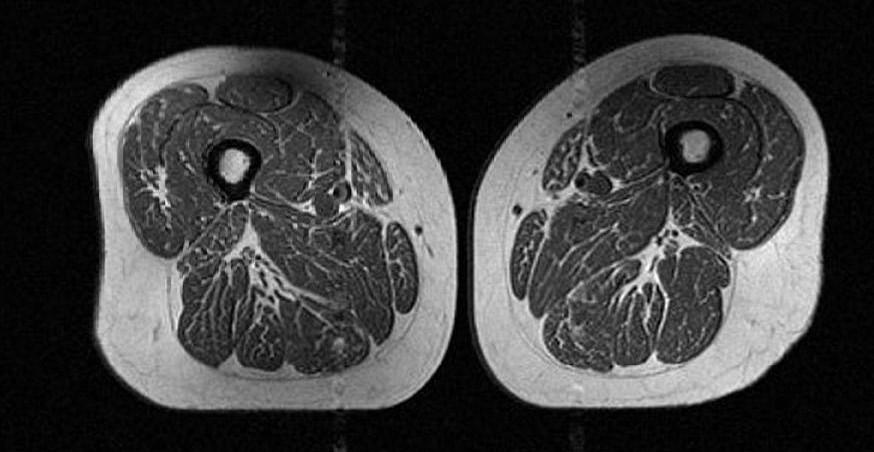

На первый взгляд это изображение можно принять за срез мраморной говядины с жировой прослойкой. Но на самом деле это МРТ-скан бедра 62-летней женщины, чей годовой рацион на 87% состоял из ультрапереработанных продуктов.

Зехра Аккая утверждает, что скрытые жировые прослойки внутри мышечных волокон и между ними могут сигнализировать о серьезных проблемах со здоровьем.

Исследование, опубликованное в журнале Radiology, проанализировало данные МРТ 615 человек. В среднем участникам было 60 лет, а их ИМТ (индекс массы тела) составлял 27 (избыточный вес).

Выяснилось, что количество калорий, потребляемое участниками, похоже, не имело значения. По словам соавтора исследования доктора Томаса Линка, чем больше ультрапереработанных продуктов ел человек, тем больше жира было в его мышцах, независимо от общего калоража.